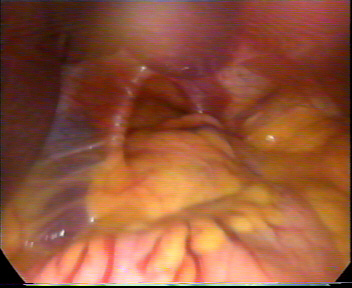

Fatta questa breve (ma indispensabile) premessa passiamo quindi a descrivere il vero argomento di questo articolo: l’ ernia iatale. L’ ernia iatale è una condizione patologica in cui una parte dello stomaco si disloca verso l’alto e, attraversato lo iato esofageo, viene a trovarsi nella cavità toracica. L’ ernia iatale da scorrimento è caratterizzata da un allargamento dello iato esofageo e dalla risalita di una porzione dello stomaco al di sopra del diaframma. Nel caso l’ ernia iatale interessi anche la sfera cardiaca, portando appunto episodi di tachicardia.

Si verifica una compressione da parte dello stomaco sull’atrio destro, azione che avviene soprattutto dopo i pasti. Ernia iatale : cause e sintomi della tachicardia. In casi più rari lo stomaco trascina con sè altri organi come la milza o il colon.